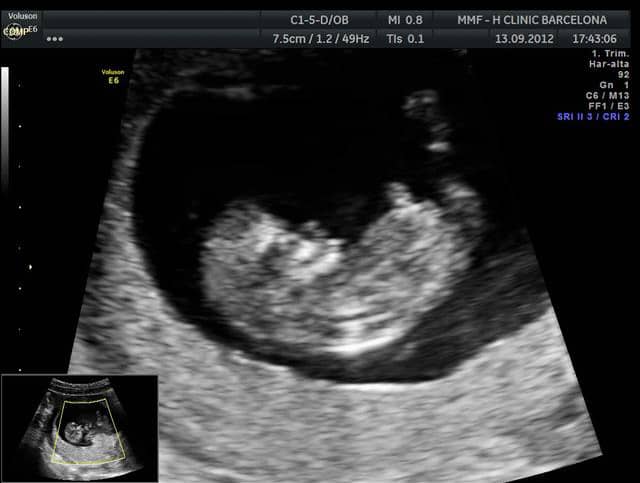

Semana 10 de embarazo ecografía. Por sus medidas se ve de 10 semanas y un día. Tamaño fetal y otras características. A partir de la semana 10 de embarazo ya se puede calcular el peso del bebé que ahora ronda los 5 gramosPuedes haber engordado algo menos de 2 kilos en estas primeras semanas.

La semana 10 de embarazo se encuentra en la mitad del tercer mes llegando ya casi al final del crítico primer trimestre. Razones para tener una ecografía de 10 semanas. Termina pues el periodo embrionario y empieza el periodo fetalTu bebé mide unos 32 milímetros desde la cabeza a la rabadilla al comienzo de la semana y pesa aproximadamente 2 gramosAl final de la semana 10 de embarazo se han formado prácticamente la totalidad de órganos y sistemas del pequeño.

Resumen de las semanas 8 11 de embarazo. Sus genitales están en proceso de finalización y pronto se podrán distinguir por ecografía. Tamaño fetal y otras características. En la ecografía de la semana 10 se pueden observar sus brazos y sus piernas pero sus manos y pies no porque son más difícil identificar. En el proceso los ligamentos y los músculos comienzan a estirarse así que no te sorprendas si empiezas a sentir algunos dolores y molestiasLos pechos probablemente te han aumentado. Cualquier factor que influya negativamente como el estrés las enfermedades incluido el SARS los medicamentos mientras está embarazada de 10 semanas es más peligroso durante las primeras 8-10 semanas. Yo personalmente considero que es demasiado tarde 12 semanas y más las primeras son muchos días donde el feto evoluciona y se produce. Por sus medidas se ve de 10 semanas y un día. Estamos en la semana 10 de embarazo y el feto ya mide unos 4 centímetros y pesa unos 5 gramos.

Ecografía hecha en UC San Carlos el 19 de mayo a las 9 semanas y 5 días. Ecografía de la semana 10. Termina pues el periodo embrionario y empieza el periodo fetalTu bebé mide unos 32 milímetros desde la cabeza a la rabadilla al comienzo de la semana y pesa aproximadamente 2 gramosAl final de la semana 10 de embarazo se han formado prácticamente la totalidad de órganos y sistemas del pequeño. En el proceso los ligamentos y los músculos comienzan a estirarse así que no te sorprendas si empiezas a sentir algunos dolores y molestiasLos pechos probablemente te han aumentado. En la ecografía de la semana 10 se pueden observar sus brazos y sus piernas pero sus manos y pies no porque son más difícil identificar. Ecografía antes de la semana 10 de gestación. Tamaño fetal y otras características.